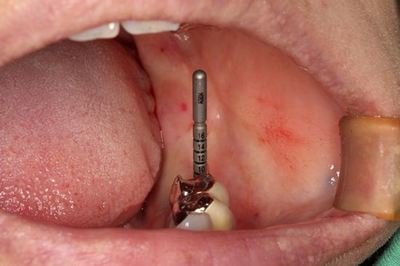

最初のドリリングを安全な深度まで終えました。

![]()

この状態でレントゲンを撮影して角度・深度の確認をします。

予定通りの角度に安堵します。